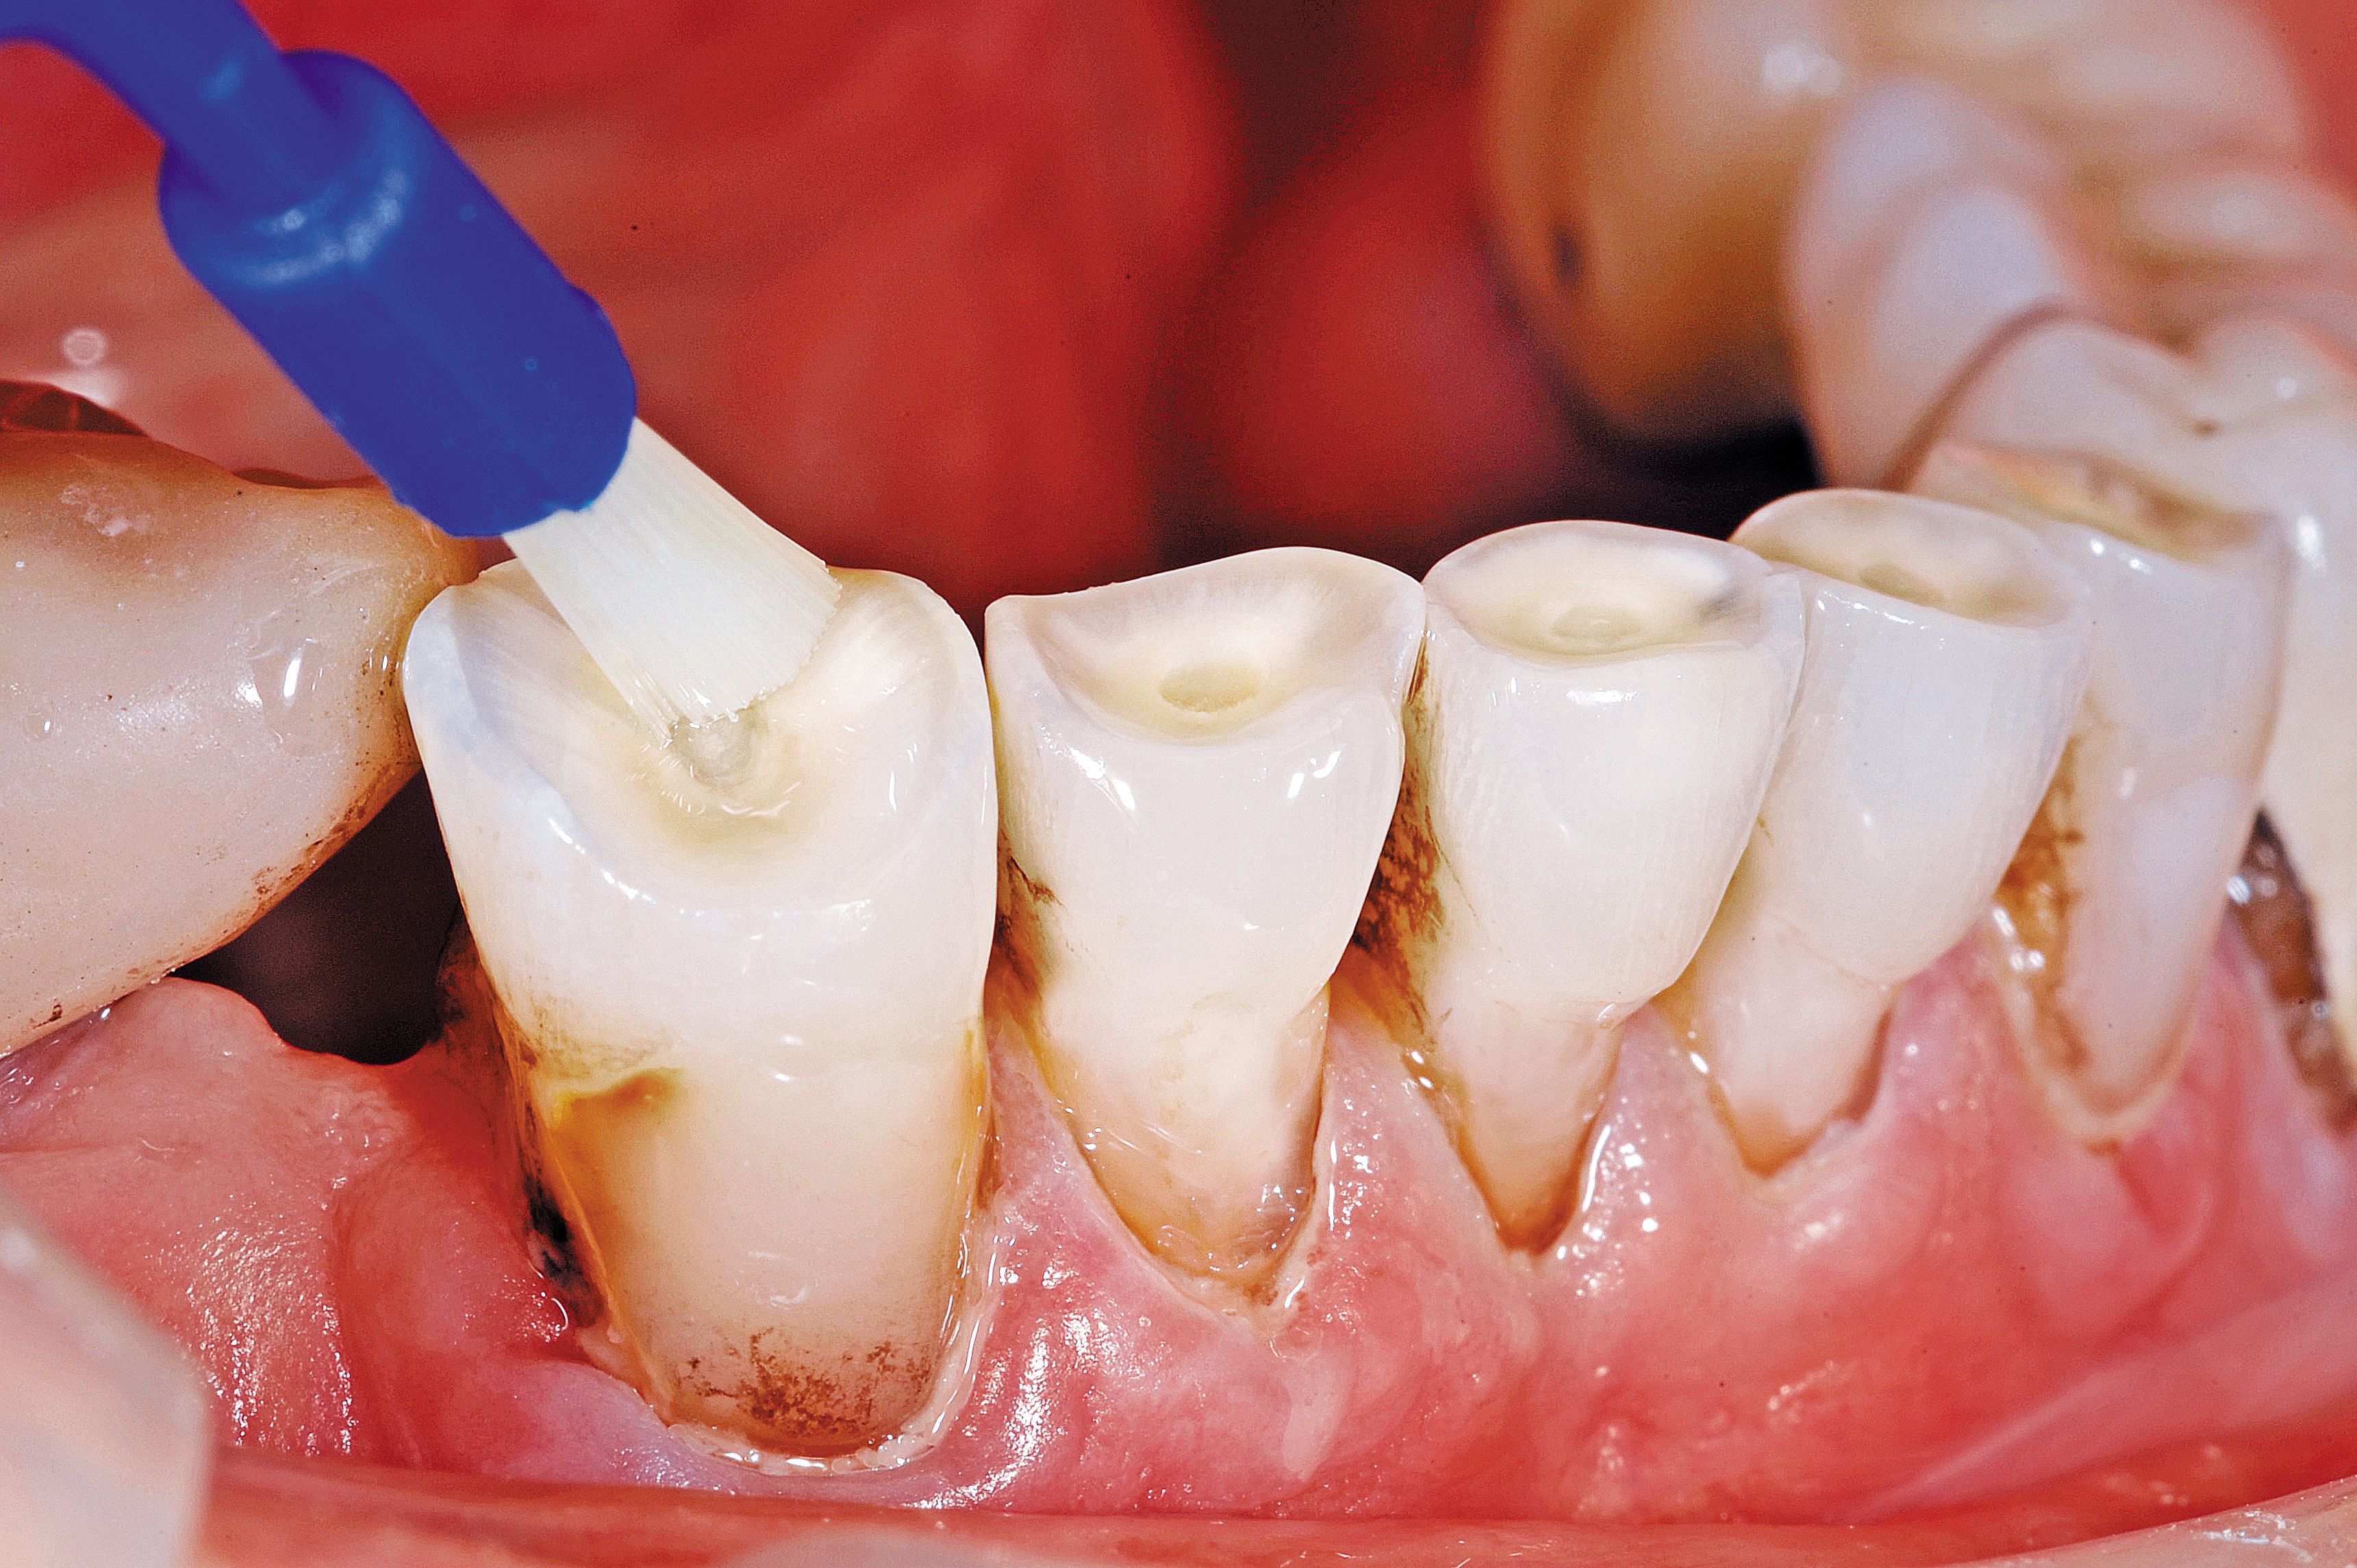

Fig. 4

The conservative nature of this treatment allows for healthy tooth structure to be maintained. By providing for the tooth surface preparation, our goal is 95 percent retention at five years of durable restorations. It must be stressed that no drilling, retention grooves or any other preparation was done at this time outside of micro-abrasion. It seems counterproductive to this practitioner to replace missing tooth structure by drilling away remaining tooth structure.

A selective-etching technique was done by etching only the enamel with 37 percent phosphoric acid for 15 seconds and then rinsed well.

The combination of acid etching of enamel and air abrasion of dentin results in frosty surfaces that provides an improved surface for bonding (Fig. 4). The surface area is greatly increased, and the contaminated outer surface is removed. Occlusal relief does not normally need to be done in these areas as the abrasion of dentin is faster than enamel, resulting in “dished out” areas that “naturally” provide ample clearance.